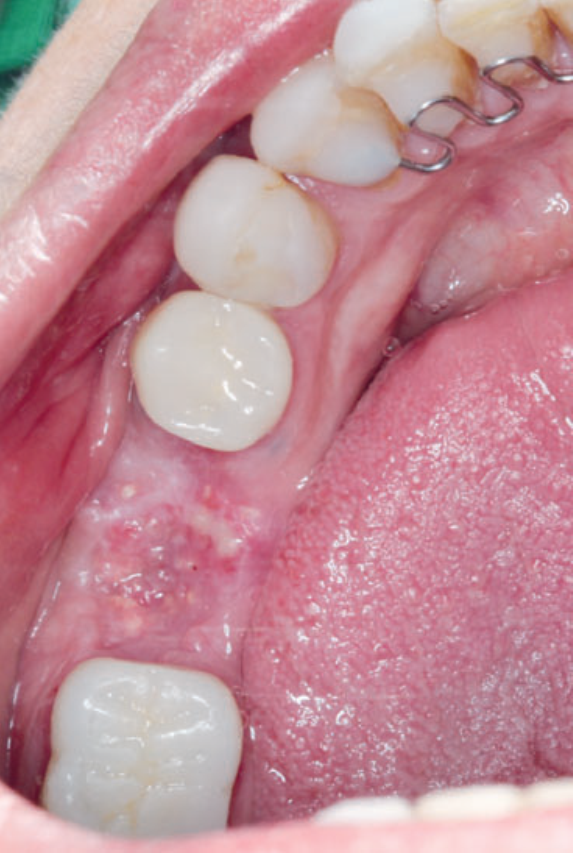

Neste relato de caso, a remoção da membrana Cytoplast foi feita aos 15 dias do pós-operatório. Depois de 23 dias, foi realizado o acompanhamento da cicatrização local (Figuras 11 e 12). Seis meses depois, a paciente voltou para realizar a reabertura da área cirúrgica (Figura 13) e retirada do parafuso de cobertura, visando à fase da reabilitação protética. Após a reabertura e remoção do parafuso de cobertura (Figura 14), e uso do Túnel Check para prótese cone-morse (estojo protético Implacil De Bortoli), foi selecionado o cicatrizador com dimensões de 4,5 mm x 5,5 mm (Figura 15) para guiar o condicionamento gengival (Figura 16). A reabilitação protética ainda está em andamento para finalização do caso (Figura 17).